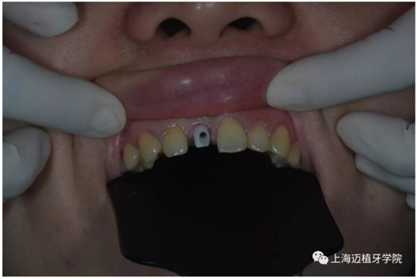

氧化鋯個(gè)性基臺(tái)

口內(nèi)個(gè)性化基臺(tái):